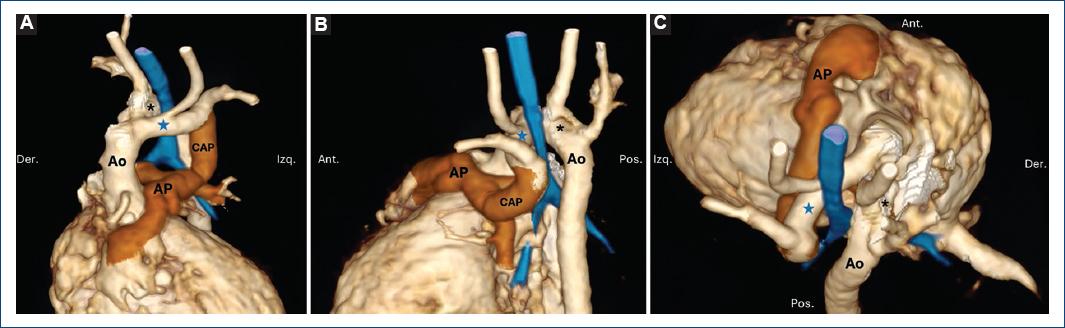

En cuanto al doble arco aórtico (Figs. 4 a 6), los subtipos fueron con dominancia derecha en el 4.5% y con dominancia izquierda en el 1.8%.

Figura 6 Doble arco aórtico: reconstrucciones volumétricas a partir de tomografía cardíaca en vista anterior (A y B), posterior-craneal (C) y lateral izquierda (D). Paciente de 4 meses en abordaje por disnea y cardiomegalia. Se documentó tronco arterioso tipo I con doble arco aórtico, el izquierdo es dominante (asterisco). En azul se representa la vía aérea; se observa compresión extrínseca a nivel del anillo vascular (flechas) y obstrucción grave en el bronquio fuente izquierdo (estrella).

El sling de la arteria pulmonar (Fig. 7) es un tipo de anillo vascular de baja frecuencia; en nuestra serie se encontró en el 1.8%, y solo la variante de sling de la rama izquierda.

Figura 7 Sling de la arteria pulmonar. Reconstrucciones volumétricas a partir de tomografía cardiaca en vista anterior (A), posterior (B) y craneal anterior con el arco aórtico seccionado (C). Paciente de 5 meses con comunicación interventricular y anillo vascular incompleto por sling pulmonar; la arteria pulmonar izquierda (asterisco) se origina desde la derecha (flechas) y tiene un curso posterior a la tráquea. En azul se representa la vía aérea. Ao: aorta; AP arteria pulmonar.